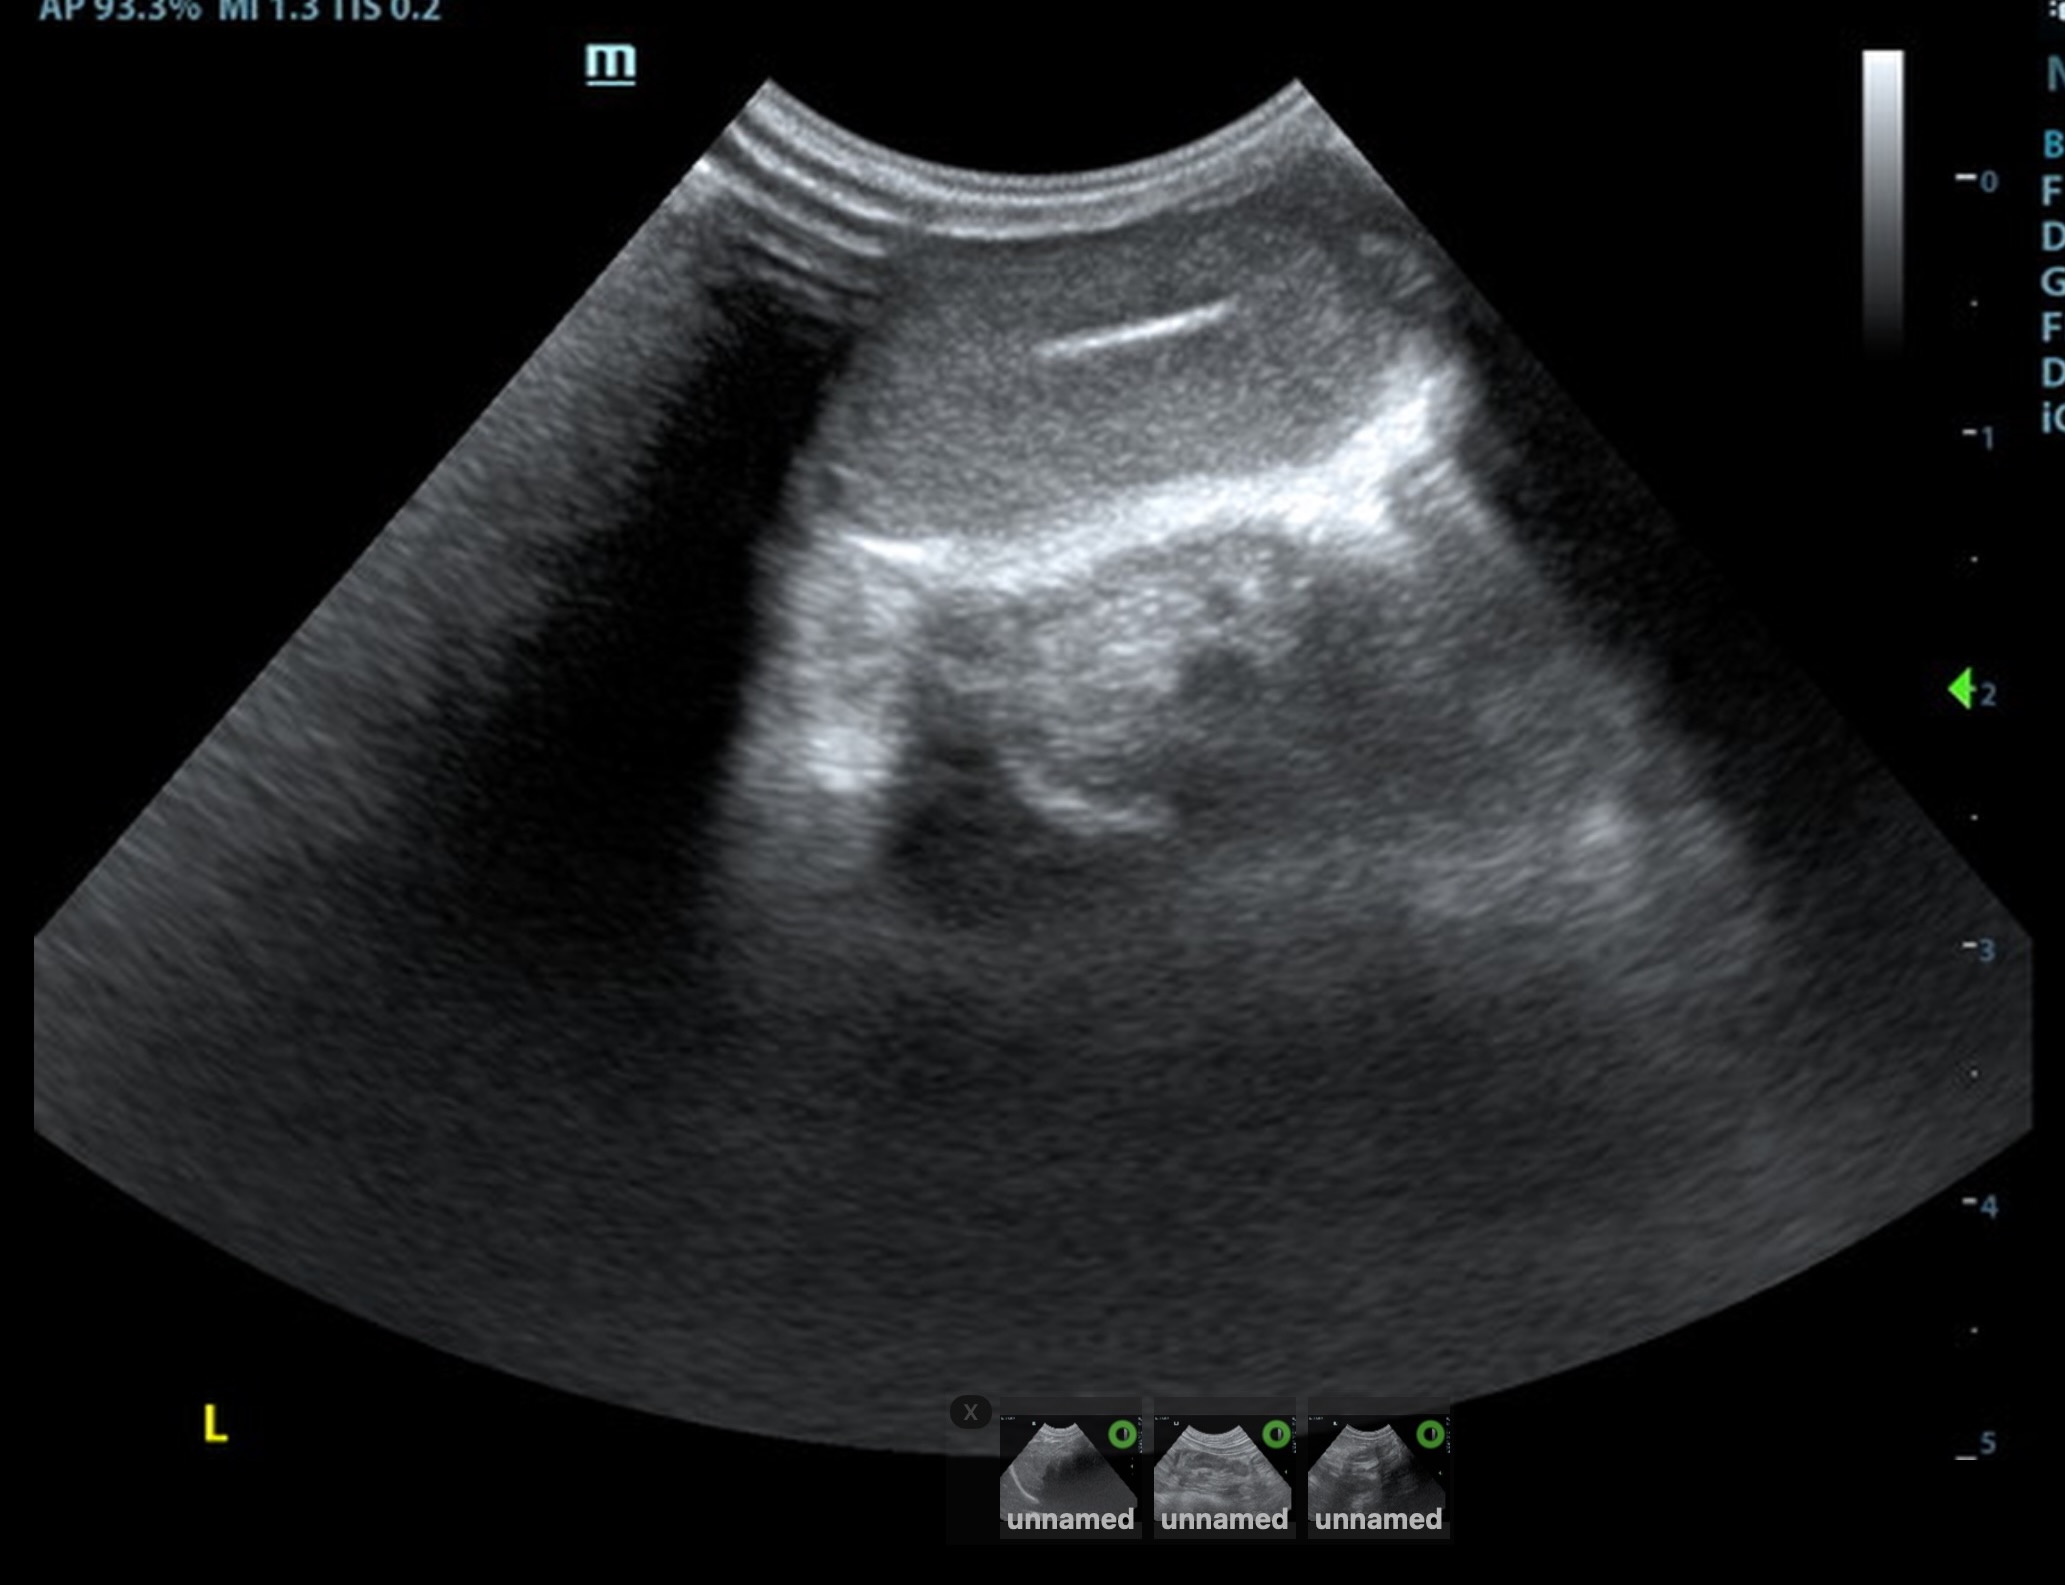

The retained testicle in this patient was midline subcutaneous inginal position, measuring approximately 1.6 cm in length and at a depth of 0.67 cm, approximately 2.0cm caudal from the cystourethral junction of the bladder. The left descended testicle was normal, measuring 1.8 cm

The mesenteric lymph nodes measured 1.5 cm x 0.5 cm. These are reactive or juvenile.